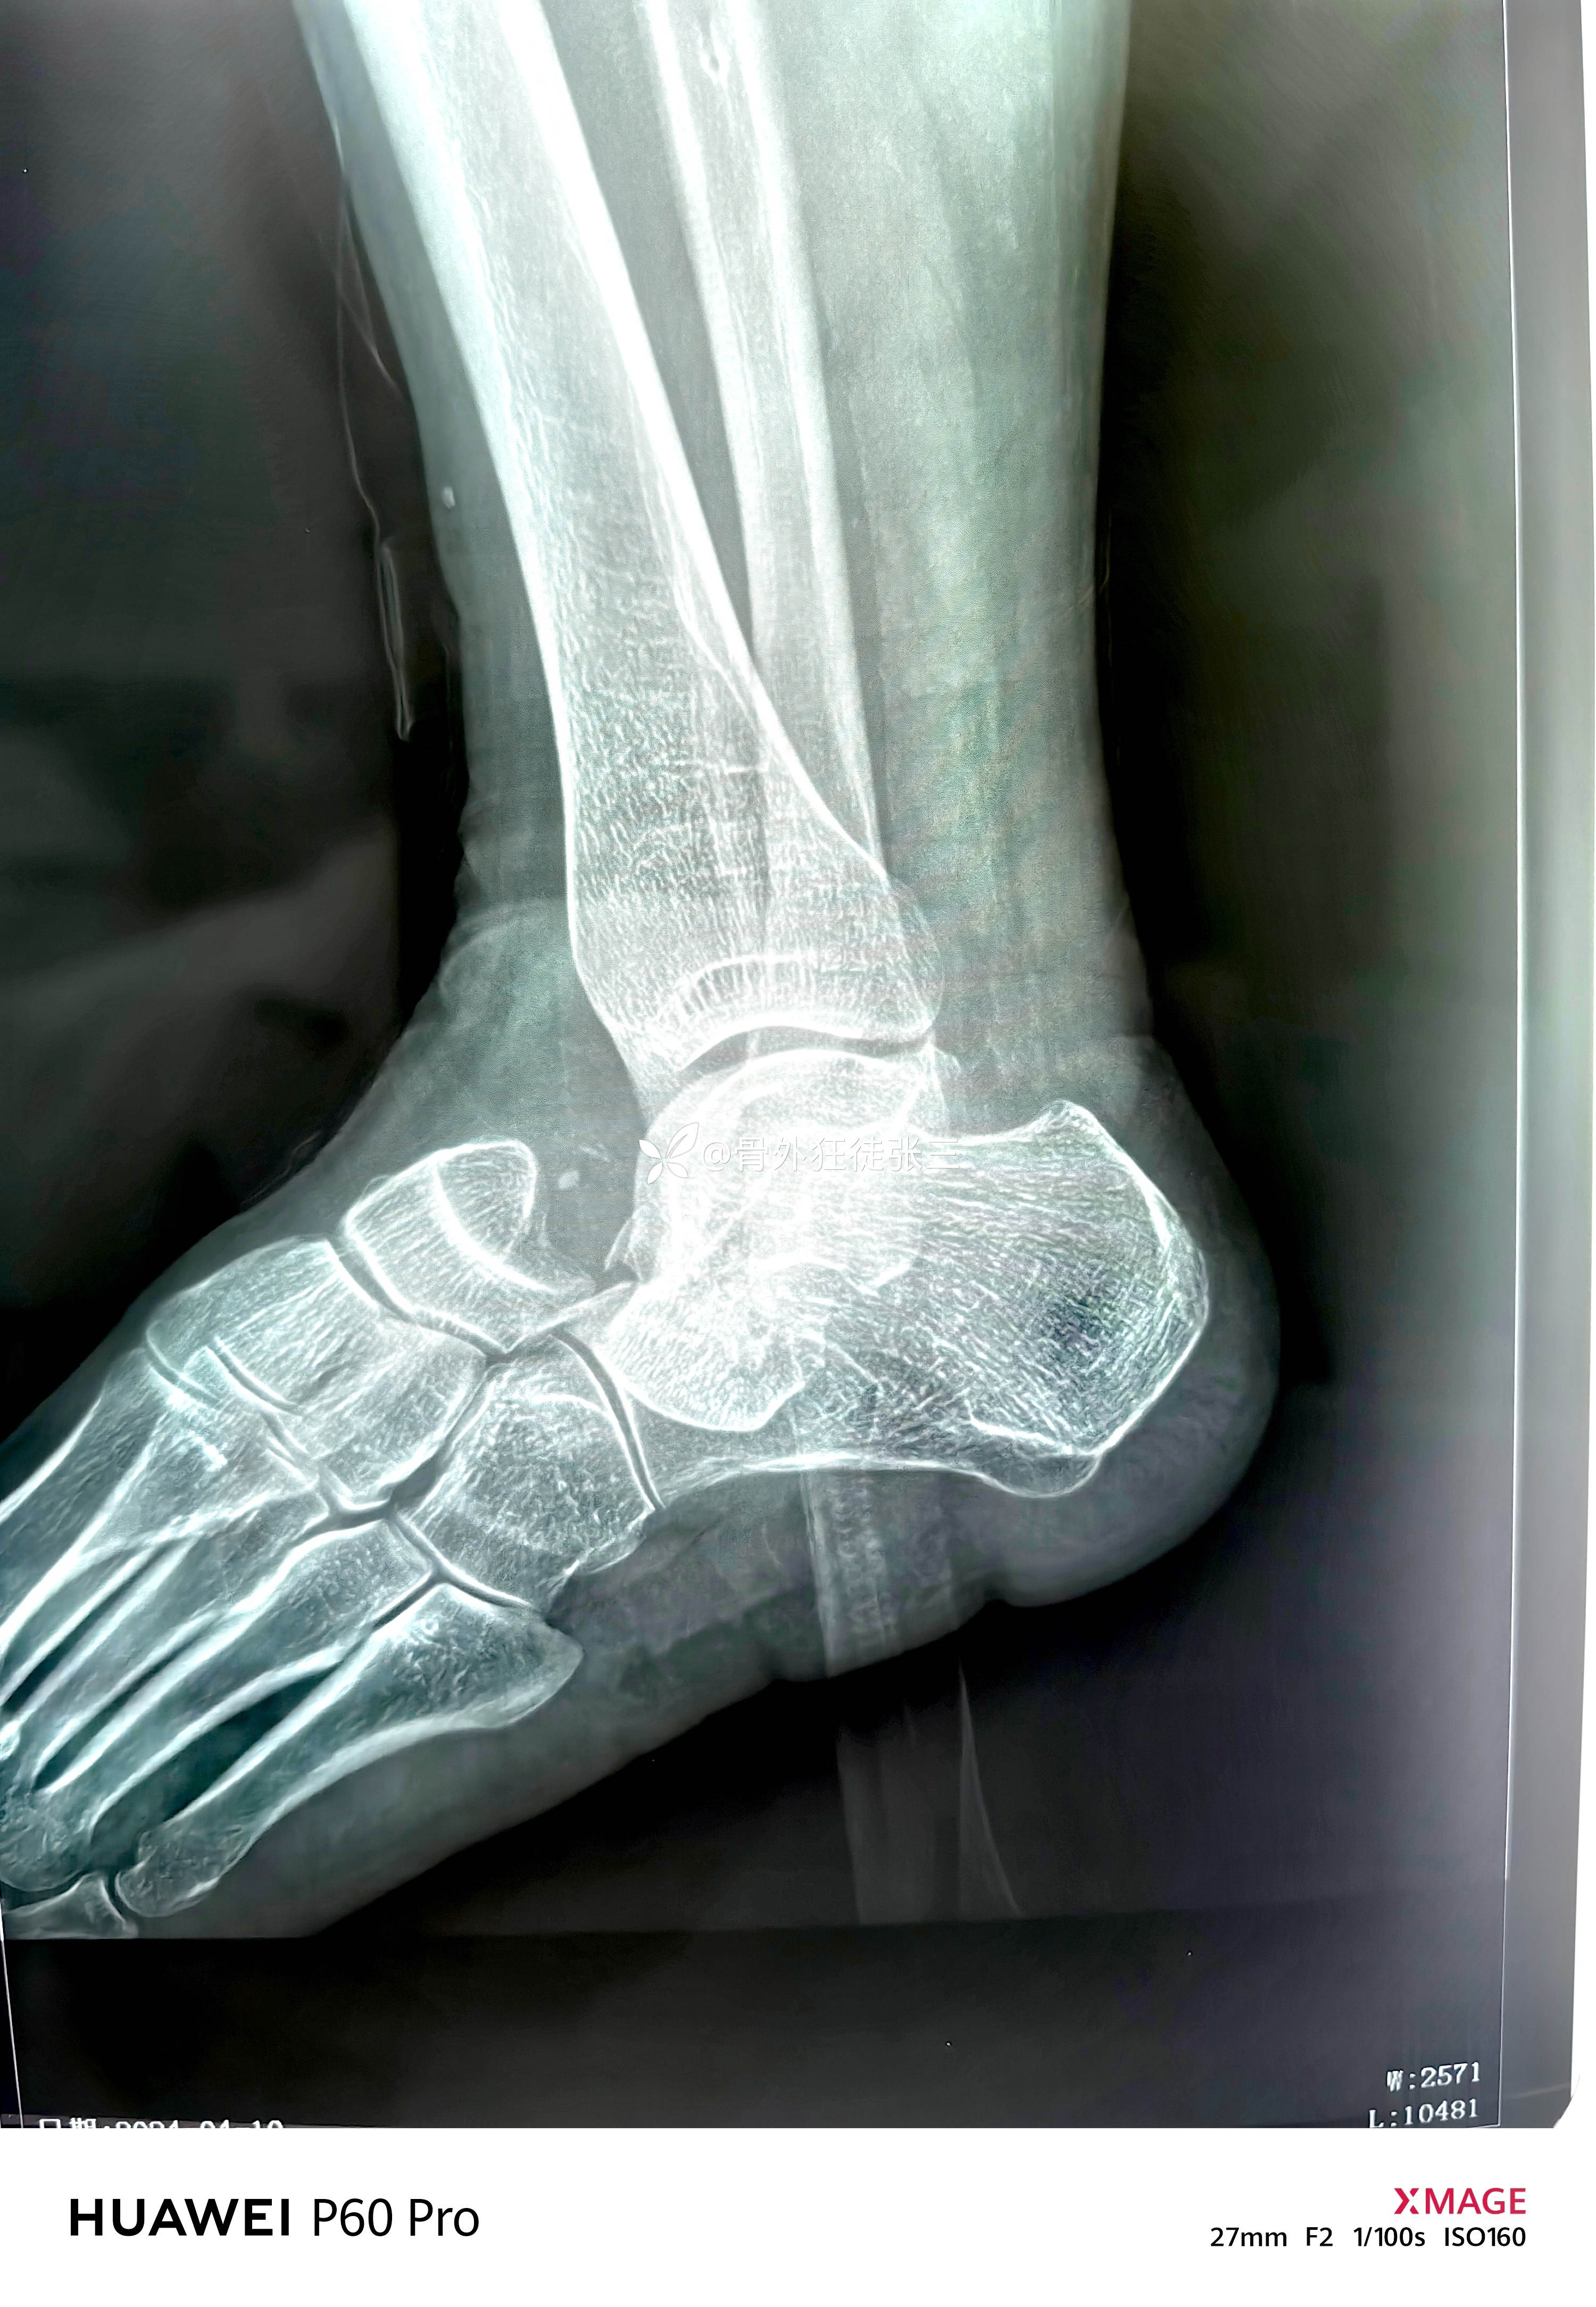

罕见损伤:距下关节脱位

主诉:车祸扭伤右踝关节致肿痛、畸形、活动受限1小时。

辅助检查:

右距下关节脱位(内侧型)